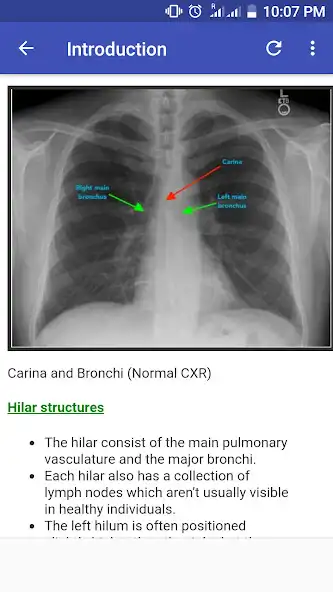

Interpreting Chest Xr-ay illustrated with cases of different pathological manifestation. It gives hint on how to comment on x-ray films. Alot of diseases has been discussed in each chapter.

Recent changes: This application made it very easy to Interpret chest x ray with illustrated 100 Cases.